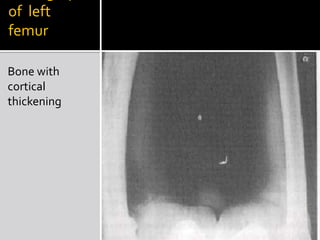

Radiograph of  left femurBone with cortical thickening